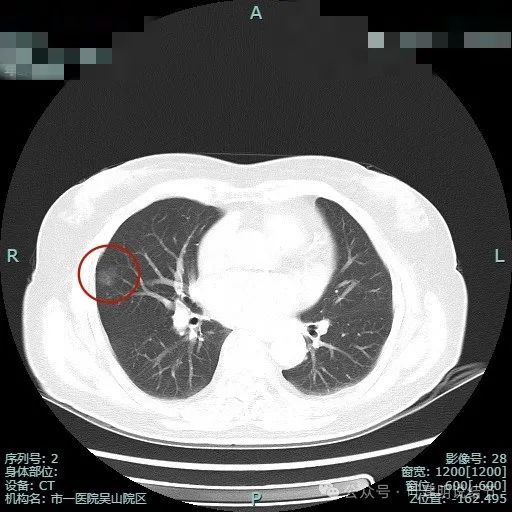

我一直认为的按密度高低来考虑病理类型危险程度,看来也有不足之处

病史摘要:患者主因“发现右侧肺部阴影3月余”就诊。3月余前当地医院体检发现右肺上叶结节,当时无明显症状。1周前于杭州市肿瘤医院复查胸部CT,提示右肺上叶磨玻璃结节,考虑MIA,偶有右侧胸部疼痛,为求进一步诊治入院。起病以来,患者神志清,精神、胃纳、睡眠及二便正常,体重无明显变化。诊疗过程:体格检查未提及。影像显示右肺上叶两处病灶,密度均较淡。临床考虑病灶2微浸润性腺癌可能性大,病灶